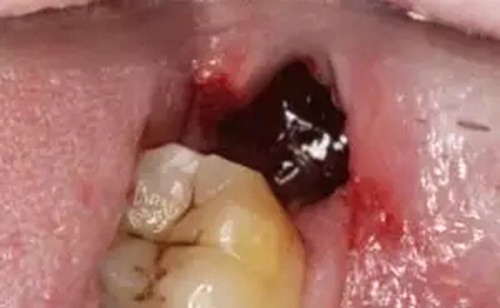

口腔照

拔牙干槽癥可怕嗎?